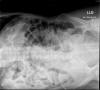

Neumonía basal.